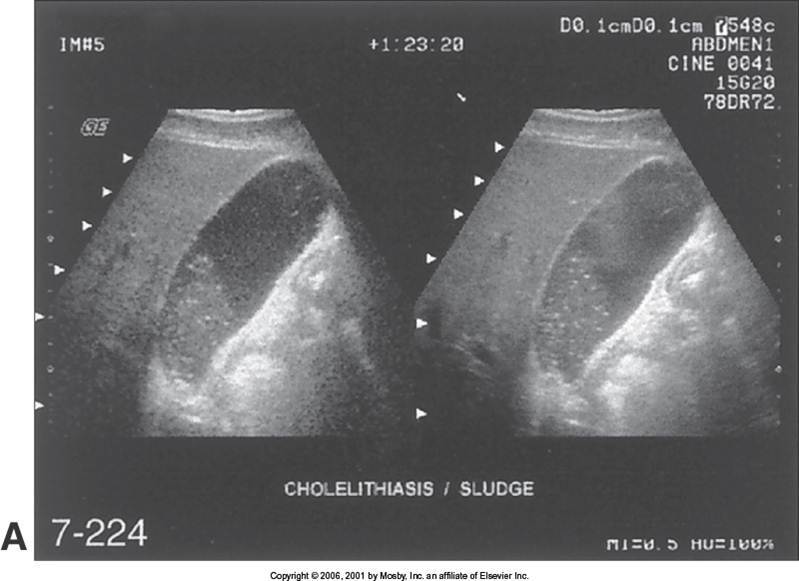

Cholelithiasis

(These small stones are “floating” on sludge

This is layering)